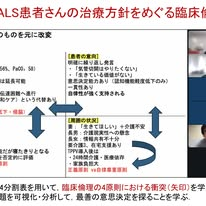

・感激した岐阜大学・名古屋大学 合同臨床実習— ALS患者さんの臨床倫理的問題をめぐって

***岐阜大学医学部下畑先生の2026年3月27日のFB投稿です***

昨日,岐阜大学と名古屋大学による合同臨床実習を開催いたしました.パンデミックを契機に始まったリモート形式の実習もすっかり定着し,両大学の強みを活かした協働教育が継続しています.今回は岐阜大学がホストを務め,脳神経内科を選択する医学部5年生5名が参加しました.

昨日,岐阜大学と名古屋大学による合同臨床実習を開催いたしました.パンデミックを契機に始まったリモート形式の実習もすっかり定着し,両大学の強みを活かした協働教育が継続しています.今回は岐阜大学がホストを務め,脳神経内科を選択する医学部5年生5名が参加しました.

実習では,当科の大野先生,國枝先生,吉倉先生の3名が指導を担当し,それぞれALS(筋萎縮性側索硬化症)の診療における「告知と遺伝子診断のあり方」「嚥下困難への対応」「進行期における意思決定」という極めて重要かつ困難な倫理的課題を提示しました.学生は事前に各自の考えをまとめたうえで参加し,ディスカッションを中心とした反転講義形式で学びを深めました.

議論の中でとりわけ印象的であったのは,告知における「知る権利」と「精神的なケア」との間にある緊張関係,そして終末期の胃瘻造設・気管切開をめぐる自己決定の問題でした.前者については,精神的に不安定な患者さんに対して,いつ,どのように告知を行うべきかという具体的な臨床場面に踏み込んだ意見が交わされました.後者では,ある学生は,認知機能低下の出現に伴って生じうる「意思の揺らぎ」にどう向き合うべきかという問題に気づきました.これは専門的な見地から言うと,「先行的自律(precedent autonomy)」と「現在の利益(current interests)」の対立という,臨床倫理のもっとも困難なジレンマのひとつと言われる問題です.

さらに,べつの学生は,患者さん一人ひとりの価値観の多様性に寄り添うためには,多職種による支援が不可欠であることにも気づき,議論を深めていました.真摯に思考を重ねる学生たちの姿に,頼もしさとともに大きな感動を覚えました.これまで低学年から行ってきた臨床倫理教育の意義を実感する機会ともなりました.

学生のうちから,このような正解のない問いに真正面から向き合った経験は,必ずや今後の医師人生を支える大きな財産になるはずです.人間味と専門性を兼ね備えた医師へと成長してくれることを,心から期待しています.